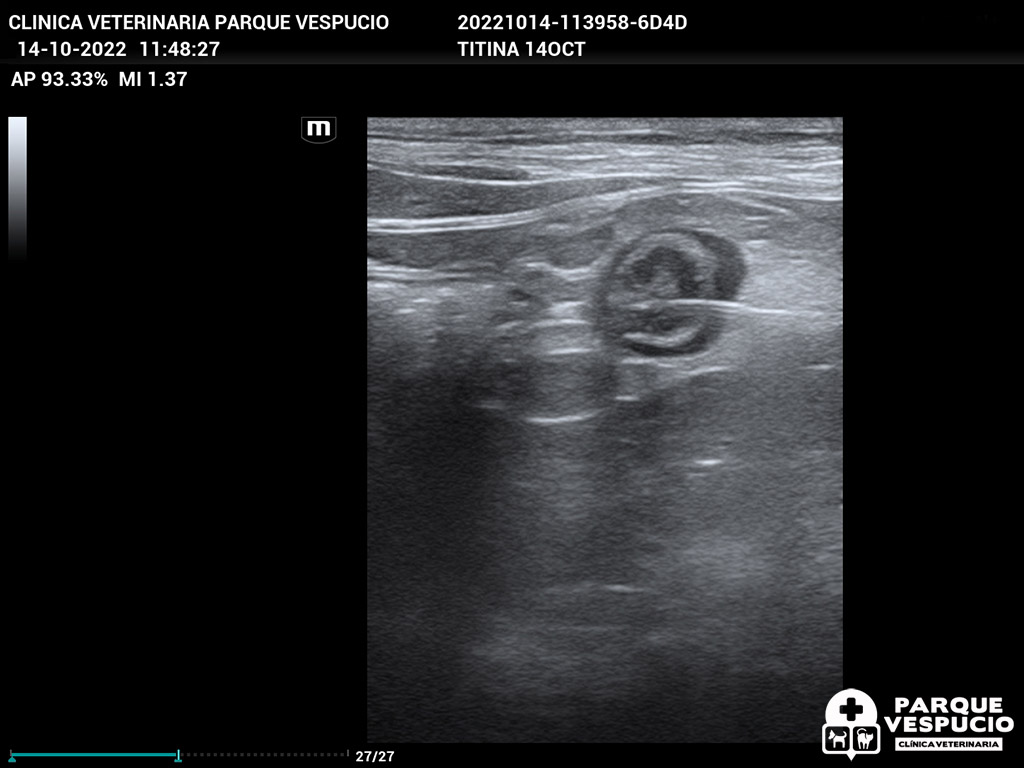

En una exploración ecográfica y radiológica de rutina, descubrimos que Titina tenía un cuerpo extraño perforante en su intestino, el cual resultó ser una aguja con hilo que había tragado accidentalmente. La situación requería atención inmediata y decidimos proceder con una cirugía para extraer la aguja.